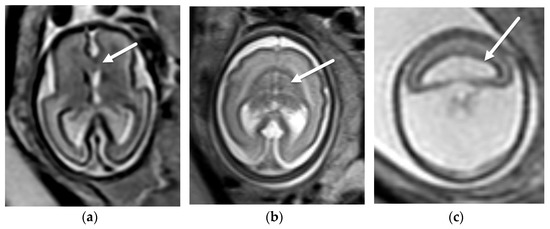

3.1.2. Chiari II Malformation

- Sutton, L.N.; Adzick, N.S.; Bilaniuk, L.T.; Johnson, M.P.; Crombleholme, T.M.; Flake, A.W. Improvement in hindbrain herniation demonstrated by serial fetal magnetic resonance imaging following fetal surgery for myelomeningocele. J. Am. Med. Assoc. 1999, 282, 1826–1831. [Google Scholar] [CrossRef] [Green Version]

- Nagaraj, U.D.; Bierbrauer, K.S.; Zhang, B.; Peiro, J.L.; Kline-Fath, B.M. Hindbrain Herniation in Chiari II Malformation on Fetal and Postnatal MRI. AJNR Am. J. Neuroradiol. 2017, 38, 1031–1036. [Google Scholar] [CrossRef] [PubMed] [Green Version]